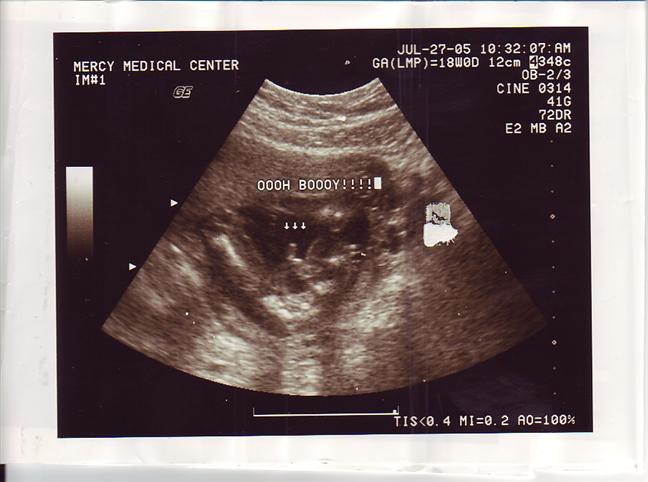

Re: sono pics of boys

Here is a pic of my son's "magic wand"..... Hope it helps! Image Attachment(s):

|